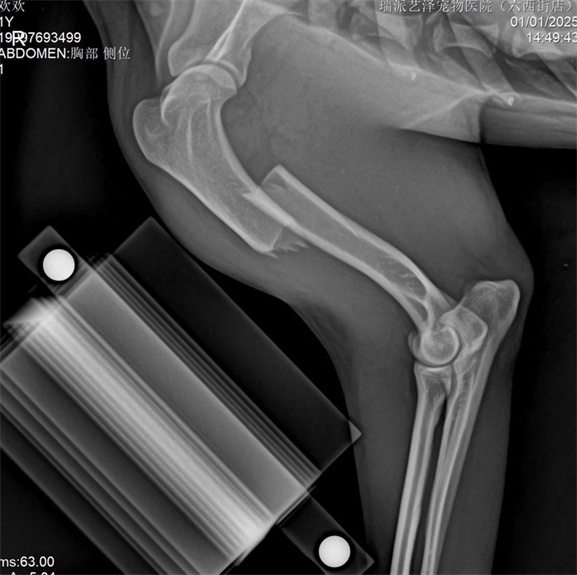

Animal basic information: Country dog, 7kg 1-year-old, cause of fracture: car accident

Right tibial shaft comminuted fracture (closed)

The tibia adopts the medial MIPO surgical approach to protect soft tissue as much as possible, and is fixed using intramedullary nails and bridging bone plates.

The tibia adopts PRCL8mm bone plate and 2.5mm needle, ensuring that there are at least two screws at the proximal and distal ends